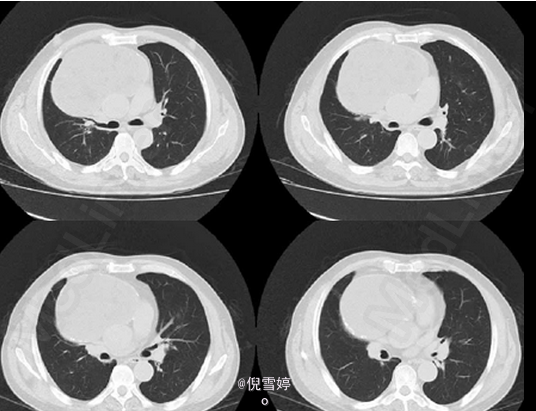

患者,男,49岁岁,因胸部不适2d就诊

患者除胸部不适外并无其他明显症状 辅查CT,右前纵隔囊性占位,多发脂肪样密度,病理检查良性

畸胎瘤 处理:手术切除